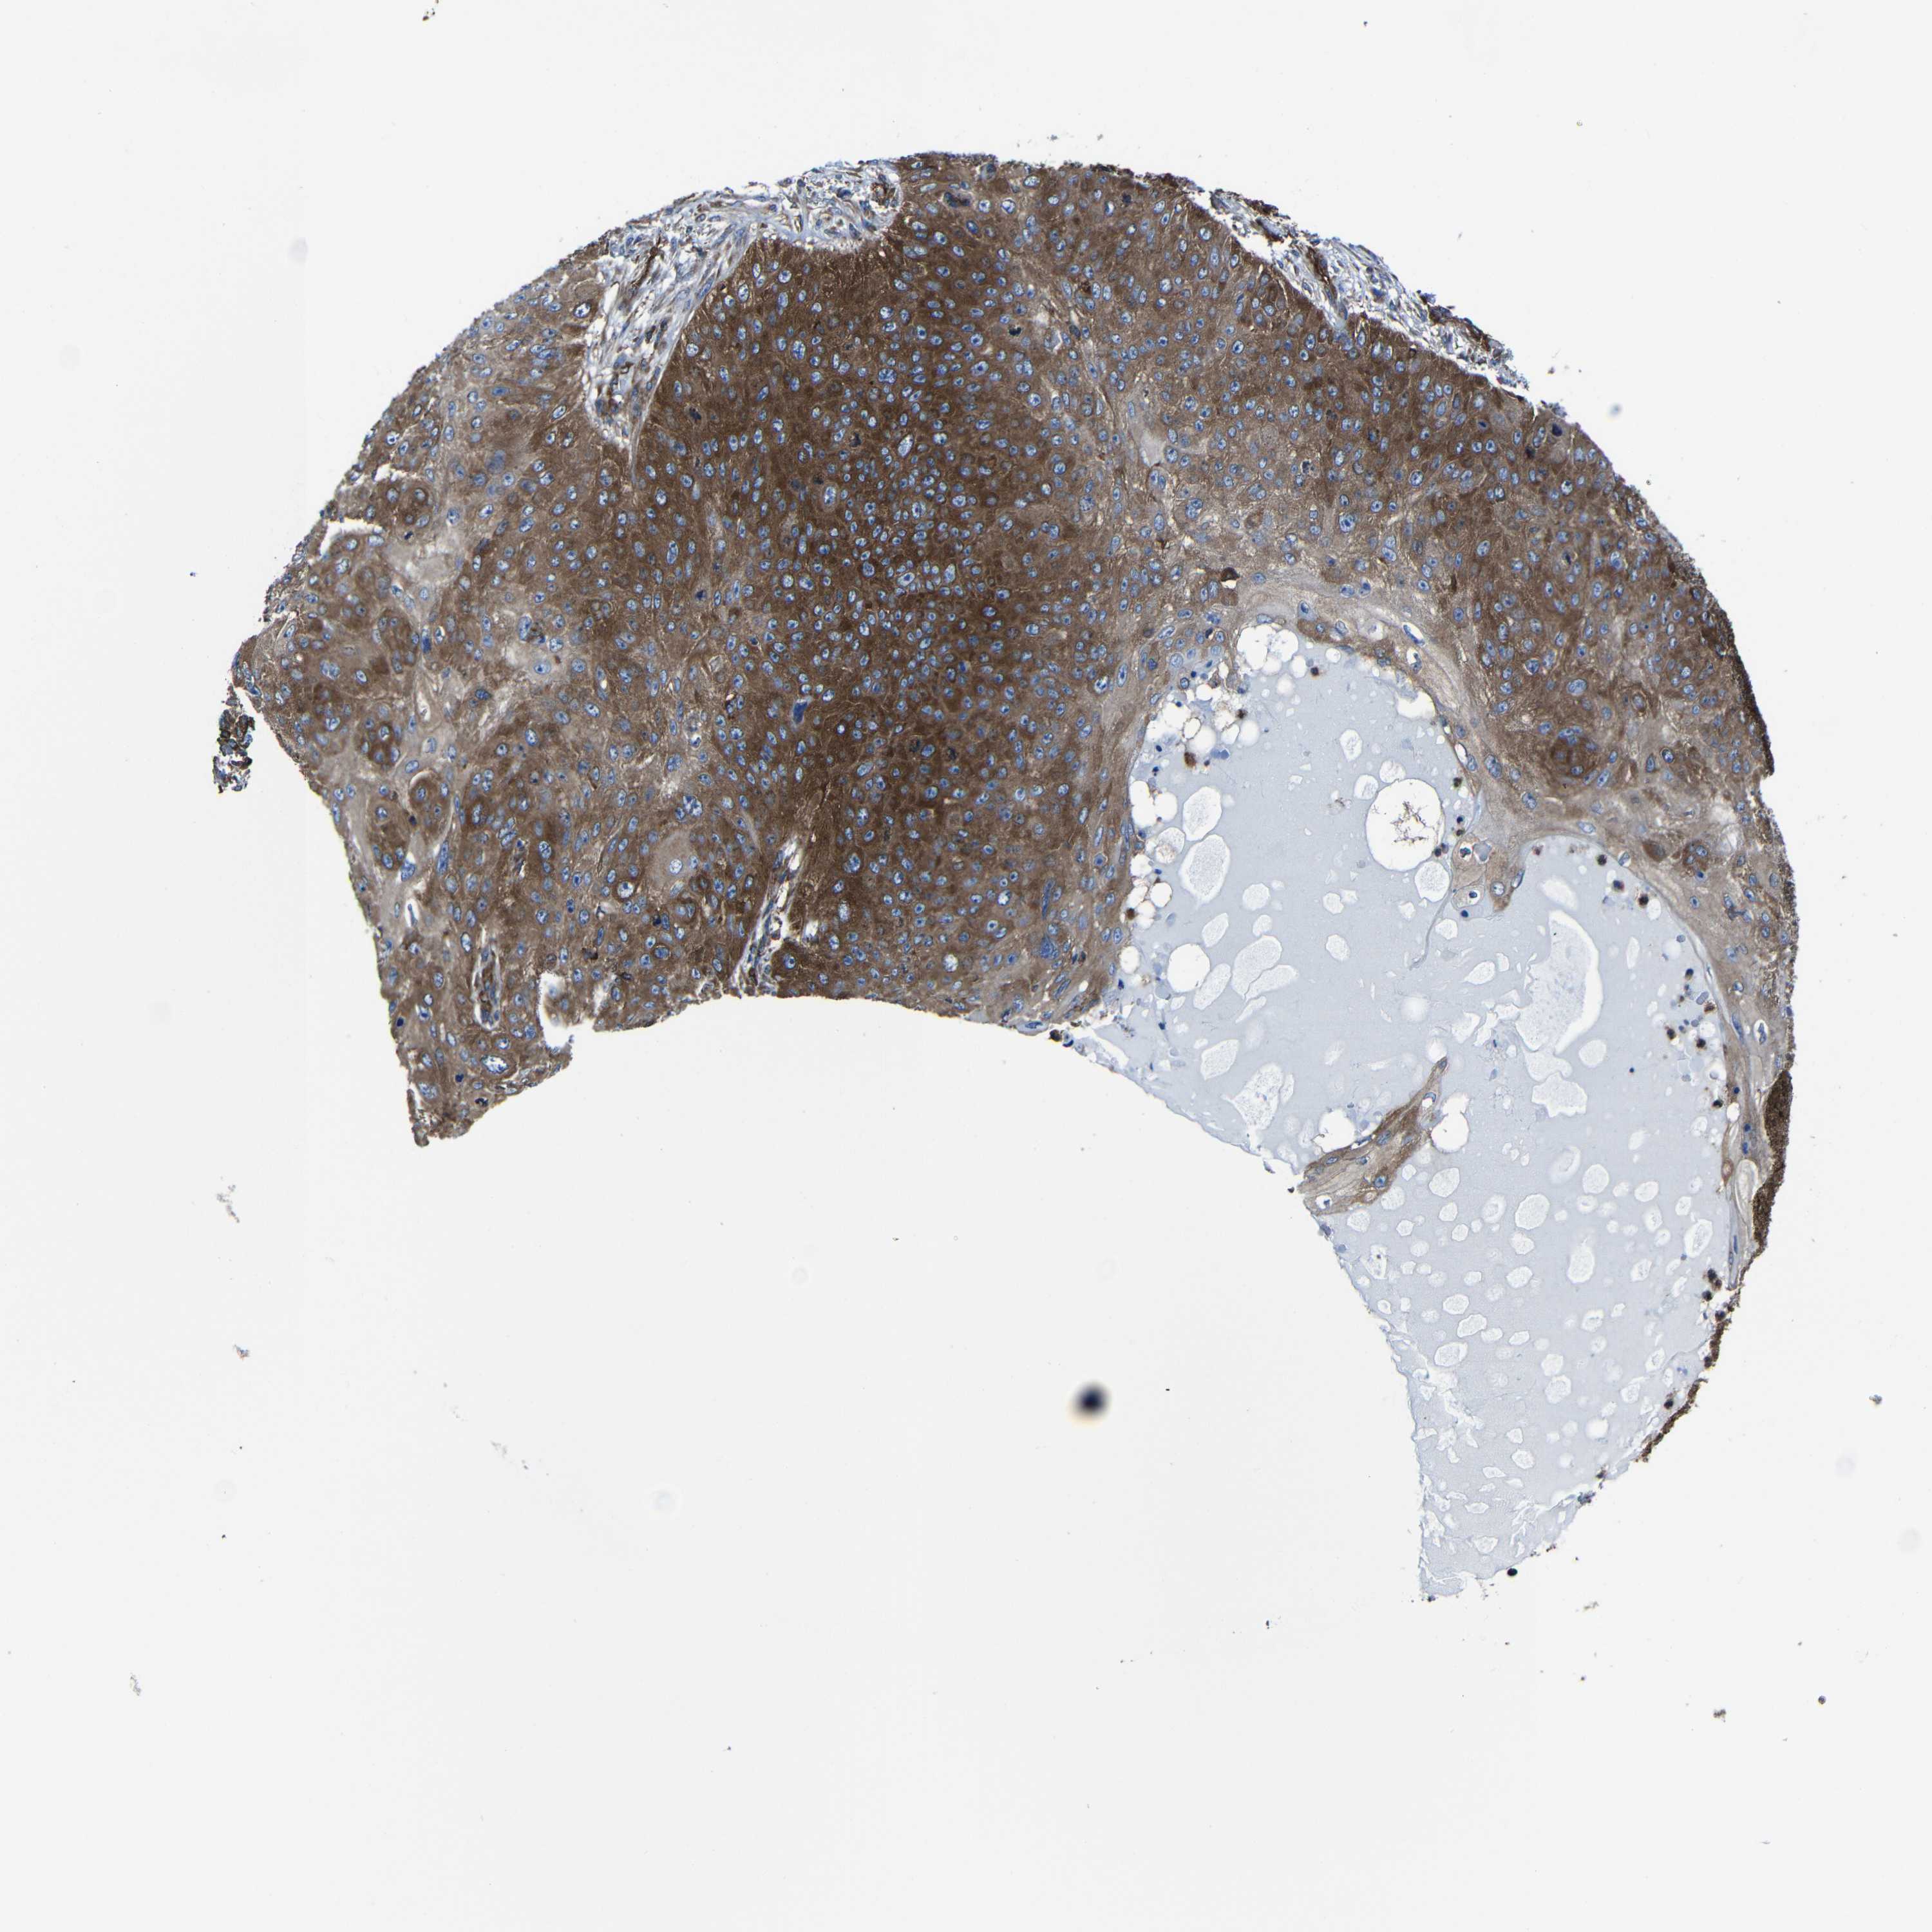

Basal cell and squamous cell cancer

SKIN CANCER - Protein expressioni

A mouse-over function shows sample information and annotation data. Click on an image to view it in a full screen mode. Samples can be filtered based on level of antibody staining by selecting one or several of the following categories: high, medium, low and not detected. The assay and annotation is described here.

Each image is clickable and will lead to virtual microscopy that enables deeper exploration of all samples and also displays staining intensity scores, fraction scores and subcellular localization as well as patient and tissue information for each sample.

Antibody CAB009502

Basal cell carcinoma